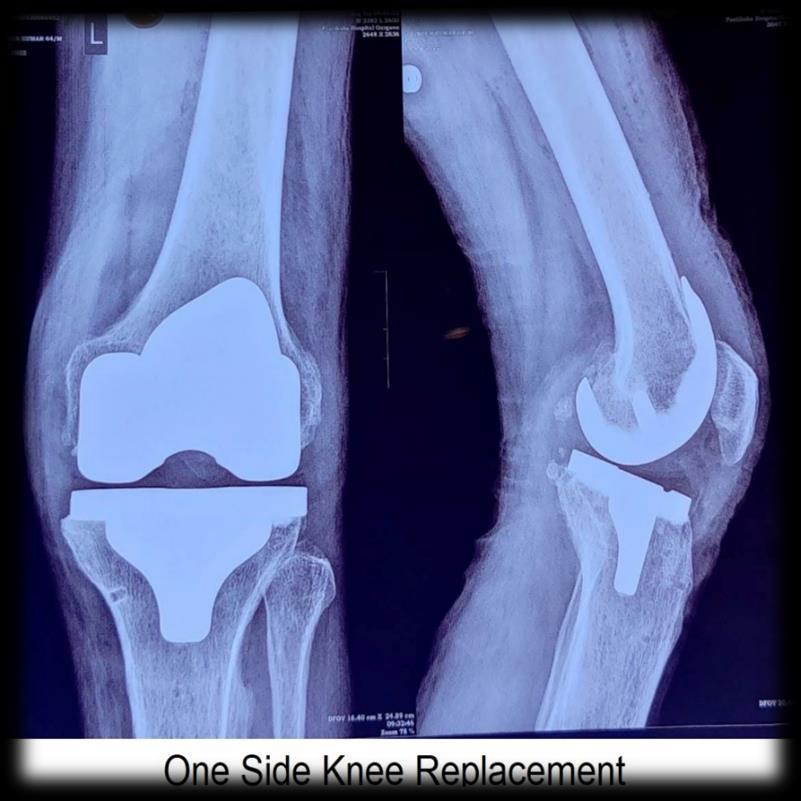

Joint Replacement Surgery

Joint replacement surgery is commonly performed these days. When they seek medical advice, they have damage to both knee joints. The patients request both knee replacement surgery at the same time. Joint Replacement Surgeon in Gurgaon have certain criteria to decide if the patient is fit to have both sides joint replacement at the same time or not. I would like to share when bilateral knee replacements should not be considered.

Two sides Knee Replacement